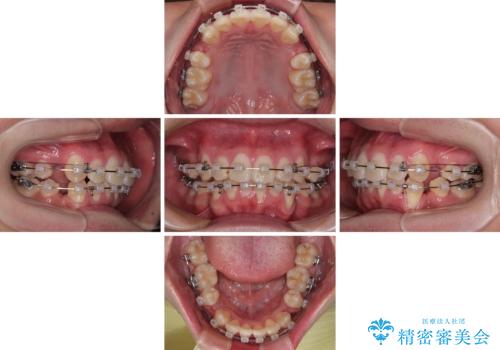

- クリアブラケット

- 1年6ヶ月

特に前歯のデコボコが顕著であり、上下左右第一小臼歯の4本を抜歯し、ワイヤー装置を使用して咬み合わせ高さを改善しながら、歯列を整えて行くこととしました。

移動が順調に進み、1年半の短期間で治療を終えることができました。